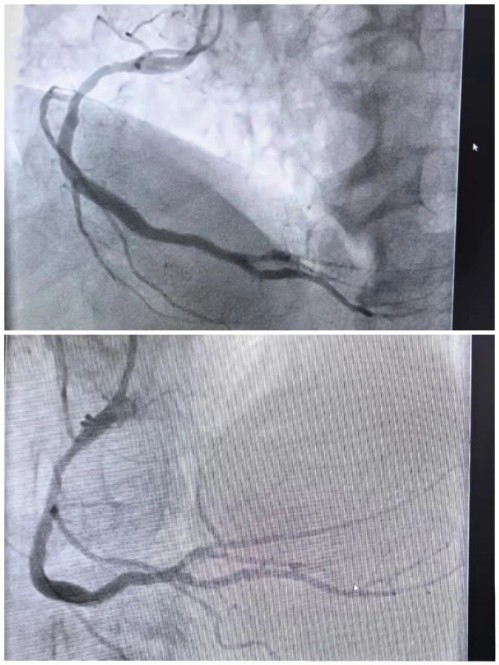

第五位患者急诊冠脉造影检查